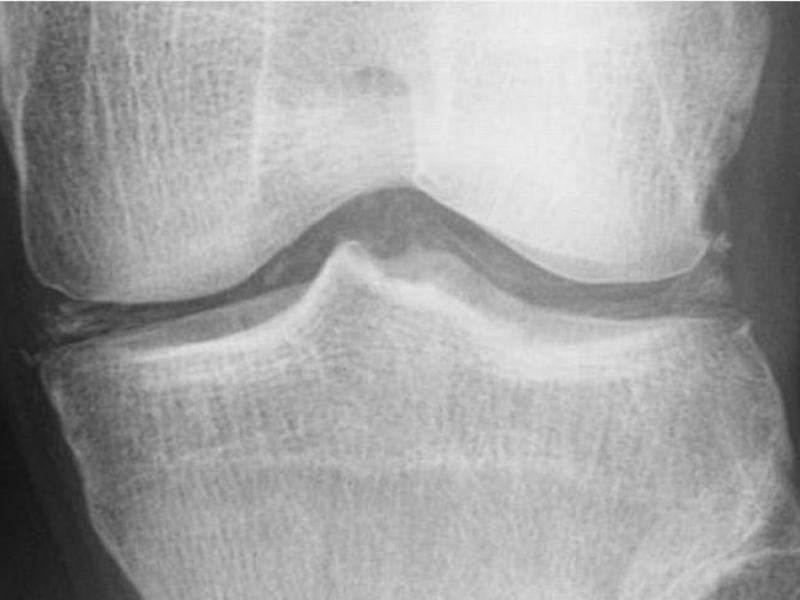

Back to Basics:  Pseudogout

Pseudogout · Aka Calcium Pyrophosphate Deposition Disease